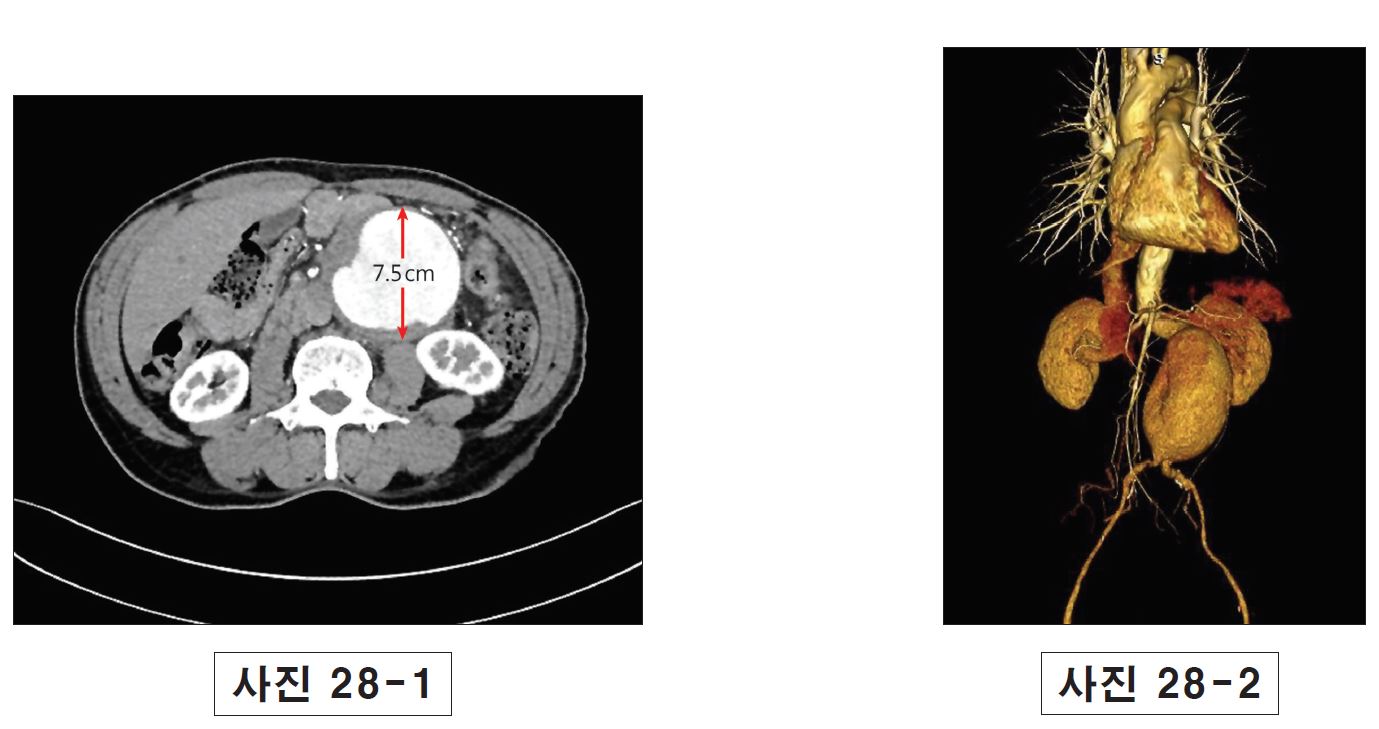

64/M, C/C Abdominal mass, pulsatile, No tenderness

박동성 있는 덩이가 만져지고 CT 상에서 명료하게 abdominal aortic aneurysm 소견. (사진 28-1, 28-2) AAA에서 치료 기준을 묻는 문제.

Tenderness 등 증상이 있을 때는 rupture 위험성 매우 높으므로 즉각적으로 repair 필요.

증상이 없을 때는 크기가 5.5cm 이상이거나 6개월 동안 0.5cm 이상 자랐을 경우 수술, 이외의 경우에는 sonography 등으로 추적 관찰.

치료에는 operative repair로 prosthetic graft 삽입(open AAA repair), endovascular aneurysm repair(EVAR) 2가지로 나뉨. Anatomy에 따라 EVAR를 선택할 수 있는데 short-term morbidity는 더 좋지만 long-term mortality는 나쁨. 최근 EVAR가 증가하는 추세로 개선되고 있으며 합병증이 적다. 따라서 ④, ⑤가 다소 애매함.

그러나 EVAR를 시행할 때 renal a.와 최소 1.5cm 이상 간격이 확보되어야 하고, mass의 크기가 6.5cm 이상일 경우 생존율 낮다고 함. (J Korean Med Assoc 2009; 52(10): 1020 – 1029) 출제자가 흉부외과임을 고려하여 가급적 open AAA repair를 우선 선택.